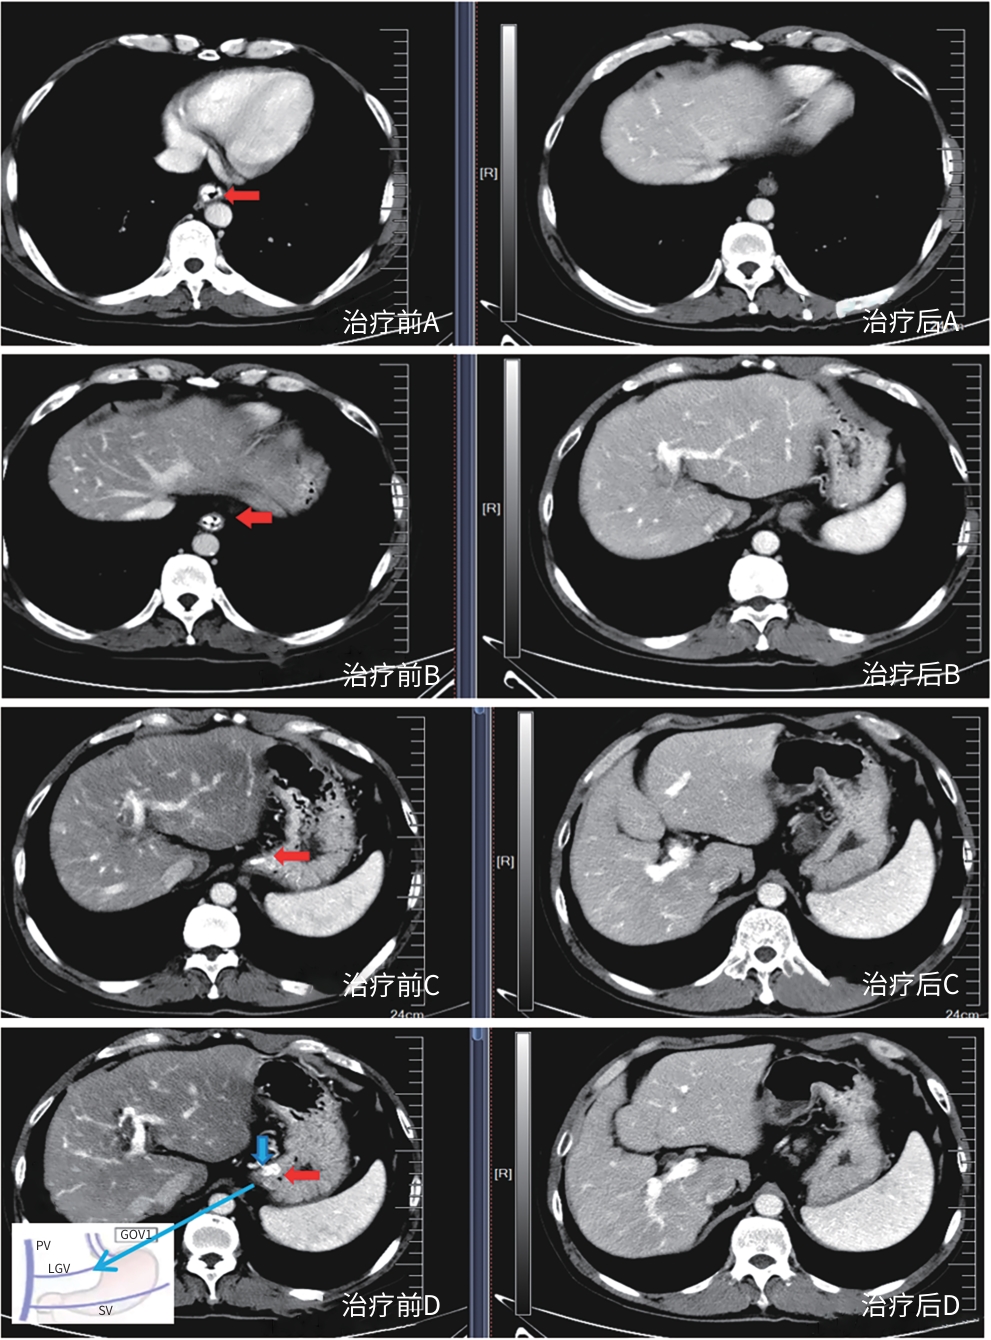

Safety and efficacy of puncture cyanoacrylate selective seal under endoscopic ultrasound versus traditional endoscopy in treatment of gastroesophageal varices: A randomized controlled trial

Jiali MA, Lingling HE, Hongshan WEI, Ping LI, Xiuxia LIANG

2025, 41(6): 1113-1119. DOI: 10.12449/JCH250617

Abstract(1039) HTML (180) PDF (1855KB)(62)

Abstract:

Objective  To investigate the safety and efficacy of puncture cyanoacrylate selective seal (PCSS) under endoscopic ultrasound in the treatment of gastroesophageal varices (GOV).  Methods  A total of 100 patients with liver cirrhosis who underwent endoscopic therapy for the secondary prevention of GOV bleeding in Beijing Ditan Hospital, Capital Medical University, from March 1 to December 31, 2023 were enrolled and randomly divided into PCSS group and traditional endoscopy group. The patients were followed up for 6 months after surgery, and the two groups were compared in terms of clinical outcome and complications. The primary outcome measure was the rate of alleviation or disappearance of GOV, and the secondary outcome measure was variceal rebleeding and death. The independent-samples t test was used for comparison of normally distributed or approximately normally distributed quantitative data between two groups, and the Wilcoxon non-parametric test was used for comparison of non-normally distributed quantitative data between two groups; the chi-square test or the Fisher’s exact test was used for comparison of qualitative data between two groups.  Results  There were 50 patients in the PCSS group, among whom 1 patient was lost to follow-up, and there were 50 patients in the traditional endoscopy group, among whom 3 patients were lost to follow-up. There were no significant differences between the two groups in baseline data such as age, sex, Child-Pugh class, varices grade, and GOV typing (all P>0.05). Compared with the traditional endoscopy group, the PCSS group had significantly better results of the number of endoscopic treatment sessions (t=-15.671, P=0.001), the total amount of tissue adhesive used (t=-2.830, P=0.006), and the rate of alleviation or eradication of varices sclerosis (χ2=7.078, P=0.029). Both groups had low rates of postoperative rebleeding, adverse reactions, and complications, and there were no significant differences between the two groups (all P>0.05).  Conclusion  Compared with traditional endoscopy, PCSS can significantly enhance treatment outcome while maintaining safety standards.